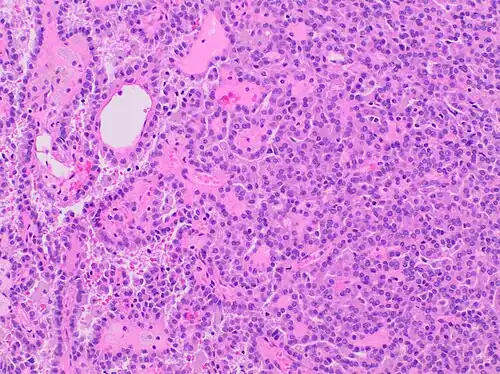

Type 1 PRCC, also known as a renal tumor caused by a genetic predisposition of hereditary papillary renal cancer syndrome, compromises approximately 25% of all PRCCs.[14][15] In the perspective of immunochemistry, it has a profile of strong CK7 and alpha-methyl acyl-CoA racemase (AMACR) expression at most focal CA-IX expression.[16] Histologically, its epithelium is composed of relatively small-sized simple cuboidal cells lined in a single layer.[17] These cells are well-characterized by basophilic cytoplasm.[18] Due to its solid growth, an extremely compact papillary architecture is often observed.[16] Other morphological characteristics include intracellular hemosiderin and foamy macrophages placed inside of papillary fibrovascular cores or psammoma bodies.[19] In general, the nuclei of type 1 PRCC belong to grade 1-2 of the Fuhrman system.[16]

A micrograph of type 1 PRCC, illustrating features of small basophilic cells with scarce cytoplasm. A single layer of cells are surrounding the basal membrane.[20] Foamy macrophages are inside of papillary fibrovascular cores.